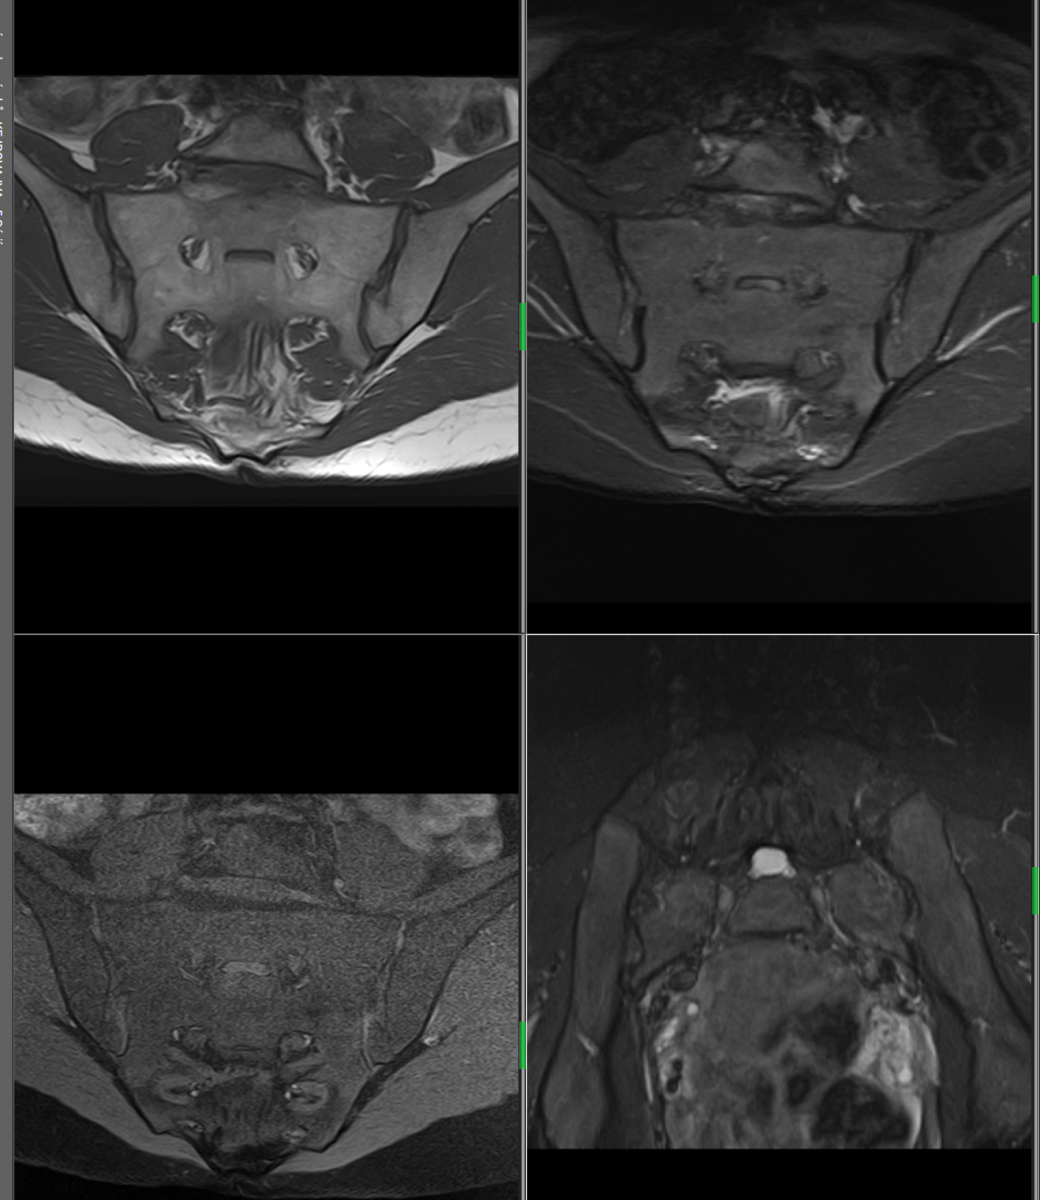

MR v břišní a pánevní oblasti

Diferenciální diagnostika jaterních lézí, cholangiopankreatografie – tzv. MRCP (neinvazivní obdoba ERCP), diferenciální diagnostika tumorů pankreatu, ledvin, staging karcinomu děložního čípku a endometria, staging karcinomu rektosigmatu, MR enterografie (u Crohnovy choroby).Rovněž se ve spolupráci s Urologickým oddělení Nemocnice České Budějovice a se specialisty místními a z okolních regionů specializujeme na diagnostiku karcinomu prostaty.